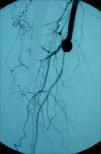

Pacientes y métodosMediante un estudio retrospectivo se analizaron los casos de los pacientes ingresados entre enero de 1999 y diciembre de 2006, con diagnóstico de isquemia crítica de las extremidades y que fueron sometidos a esta técnica quirúrgica, en quienes se llevó a cabo una revascularización protésica de la AFP distal con interposición de cuff de Miller (Fig. 1). Se definió la isquemia crítica como la existencia de dolor en reposo persistente, de úlceras o de gangrena por isquemia crónica, atribuibles a una enfermedad oclusiva definida por métodos objetivos (definición clásica de consenso TASC), pero sólo se consideraron candidatos con posibilidades de lograr una revascularización suficiente los pacientes que presentaban exclusivamente dolor en reposo o lesiones mínimas de gangrena distal. Los casos con gangrenas extensas se desestimaron.

Se utilizó la técnica por alguno de los siguientes motivos: ausencia de pulso femoral homolateral o importante disminución de éste (en general con procedimientos previos de revascularización femoral tardíamente fallidos) e imposibilidad de poder realizar una revascularización infragenicular o maleolar ante la escasa probabilidad de éxito técnico, por no observarse en la angiografía retardada un segmento de tronco distal que llegase hasta el pie o por la ausencia de material autólogo. En estos casos se decidió dicho procedimiento como alternativa a la amputación. Desde el punto de vista angiográfico, las características fueron enfermedad oclusiva del eje ilíaco, recanalización en la AFP distal con buena colateralidad, trombosis de femoral superficial y recanalización infragenicular, con troncos distales lesionados que no se consideraron susceptibles de ser intervenidos mediante cirugía directa.